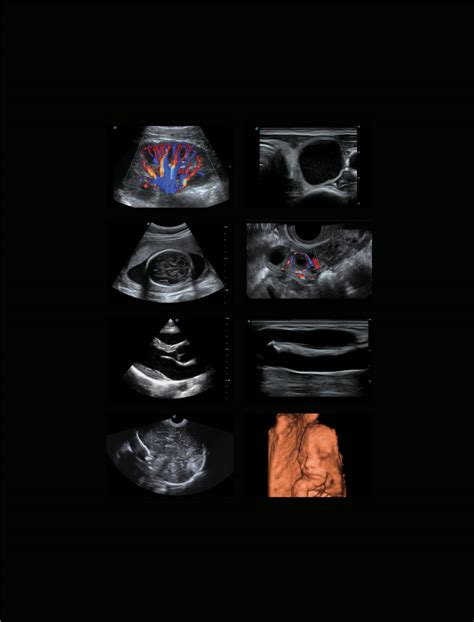

Alright, let’s geek out a bit on the tech. When we talk about Sonoscape ultrasound machines , we’re talking about serious engineering. These guys pack features like high-density transducers , which means you get super-detailed images. Imagine seeing even the tiniest anomalies with incredible clarity – that’s what these transducers do. Then there’s their advanced image processing technology . This isn’t just about capturing the image; it’s about enhancing it, reducing noise, and sharpening the details so you can make confident diagnoses. Think of it like having a super-smart filter that automatically makes everything look better and clearer. They also focus heavily on Doppler capabilities , which are crucial for visualizing blood flow. Whether it’s color Doppler, power Doppler, or pulsed-wave Doppler, Sonoscape machines offer robust options for assessing vascular health, heart function, and much more. This level of detail is absolutely critical for conditions ranging from deep vein thrombosis to fetal well-being. Furthermore, Sonoscape is constantly innovating. They’re integrating AI-powered features, improving ergonomics for comfortable use during long procedures, and developing portable ultrasound solutions that bring high-end imaging capabilities right to the patient’s bedside or remote locations. The commitment to research and development is evident in the sophistication and reliability of their products. It’s this blend of sophisticated hardware, intelligent software, and a user-centric design philosophy that truly sets Sonoscape apart in the competitive landscape of medical imaging. They consistently strive to deliver tools that are not only technologically advanced but also intuitive and practical for everyday clinical use, ensuring that the benefits of their innovation reach both the practitioner and the patient effectively and efficiently.

For day-to-day diagnostics, Sonoscape’s general imaging ultrasound machines are the stars. These are your go-to systems for a broad range of applications, including abdominal, obstetrics, gynecology, and small parts imaging. Brands like the Sonoscape S-Series (think S20, S25, S30) are incredibly popular. Why? Because they strike that perfect balance between powerful performance and affordability. You get excellent image quality, a user-friendly interface that doesn’t require a PhD to operate, and a robust set of features that can handle most common diagnostic scenarios. These machines often come with a variety of probe options, allowing you to tailor the system to your specific clinic’s needs. The intuitive control panel and streamlined workflow mean less time spent fiddling with settings and more time focused on the patient. Many of these models also offer impressive Doppler capabilities, essential for evaluating blood flow in various organs and pathologies. Plus, their ergonomic design ensures comfort for the sonographer during extended use. For clinics and hospitals looking to enhance their diagnostic capabilities without a massive capital outlay, these general imaging units from Sonoscape Indonesia are an absolutely brilliant choice. They represent a smart investment in reliable, high-quality diagnostic tools that can significantly improve patient care and diagnostic confidence across a multitude of medical disciplines. The versatility and reliability packed into these machines make them indispensable assets in any modern healthcare setting seeking to optimize both efficiency and diagnostic accuracy.

Beyond general imaging, Sonoscape Indonesia also excels in providing specialized ultrasound solutions. These machines are designed with precision and advanced capabilities for specific medical fields. For instance, their cardiac ultrasound systems are built to provide exceptional detail for echocardiography, helping cardiologists assess heart structure and function with remarkable accuracy. Think high frame rates, advanced Doppler modes, and specialized cardiac probes. Then you have their urological ultrasound offerings, which might include features tailored for prostate imaging or other specific needs in urology. Sonoscape also offers systems geared towards veterinary medicine , recognizing the unique requirements of animal imaging. The beauty of these specialized systems is that they leverage Sonoscape’s core imaging technology but refine it with features and workflows optimized for a particular specialty. This means you’re not just getting a generic ultrasound; you’re getting a tool engineered to excel in its specific application. This focus on specialization allows healthcare professionals to achieve a higher level of diagnostic certainty and potentially discover conditions that might be missed on less specialized equipment. The availability of these advanced tools through Sonoscape Indonesia empowers specialists to push the boundaries of their practice, offering cutting-edge diagnostic services to their patients and contributing to better health outcomes. Investing in a specialized Sonoscape unit is a testament to a commitment to excellence within a particular field of medicine, ensuring that practitioners have the very best technology at their fingertips to tackle the most complex diagnostic challenges with confidence and precision.